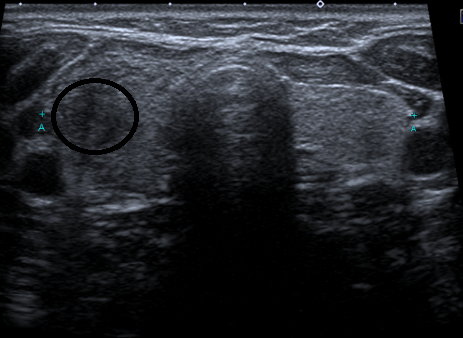

6 years ago, my constant neck pain has warranted me to seek doctor advice. I was diagnosed with a 2.2 cm tumour in my right thyroid. 😰

The only good news is the growth is benign.

2 years after the diagnosis, the tumour disappeared.